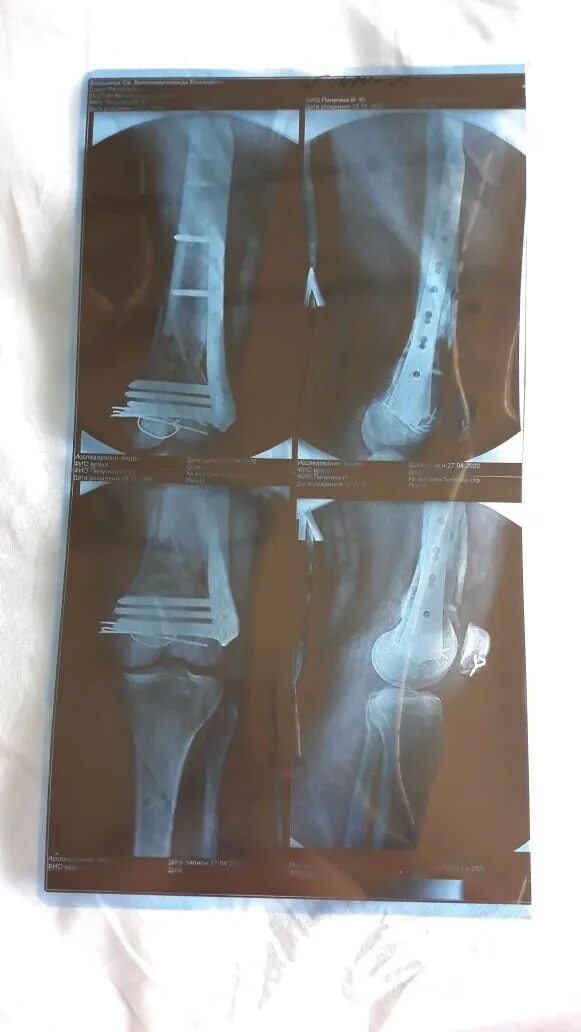

Оскольчатый перелом со смещением